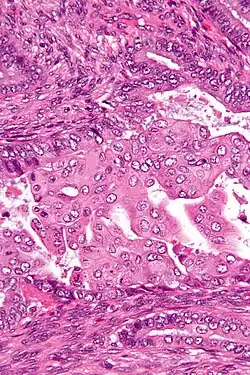

Endometrial adenocarcinoma (carcinoma at left in image) with squamous differentiation evidenced as necrotic “ghost cells” of keratinocytes at right in image, leaving pink keratin as well as clear spaces at the prior locations of the cell nuclei.